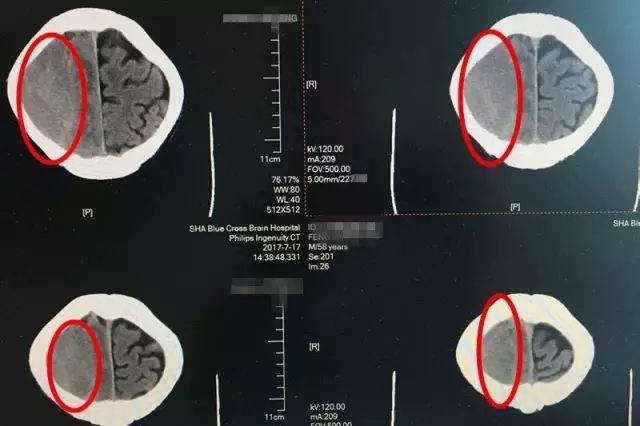

即便如此,時(shí)間不等人,等到七月中旬老馮一家輾轉(zhuǎn)打聽(tīng)到上海藍(lán)十字腦科醫(yī)院,慕名找到神經(jīng)內(nèi)科的李振并主任時(shí),老馮的癥狀已經(jīng)開(kāi)始加重了。入院時(shí)的腦CT影像檢查顯示,患者出血量增加,腦中線明顯移位變質(zhì),左側(cè)肢肌力3級(jí)(在和地心引力相反的方向中尚能完成其動(dòng)作,但不能對(duì)抗外加的阻力),而且,他開(kāi)始出現(xiàn)嗜睡、不思飲食的情況,如果再不及時(shí)治療,患者很可能會(huì)陷入昏迷、偏癱、失語(yǔ)、癲癇,巨大的風(fēng)險(xiǎn)正一步一步靠近。因此,迅速制定合理的治療方案,才能及時(shí)挽救患者。

患者術(shù)前CT影像顯示:紅圈處為腦出血部位,出血量較大,顱內(nèi)壓升高